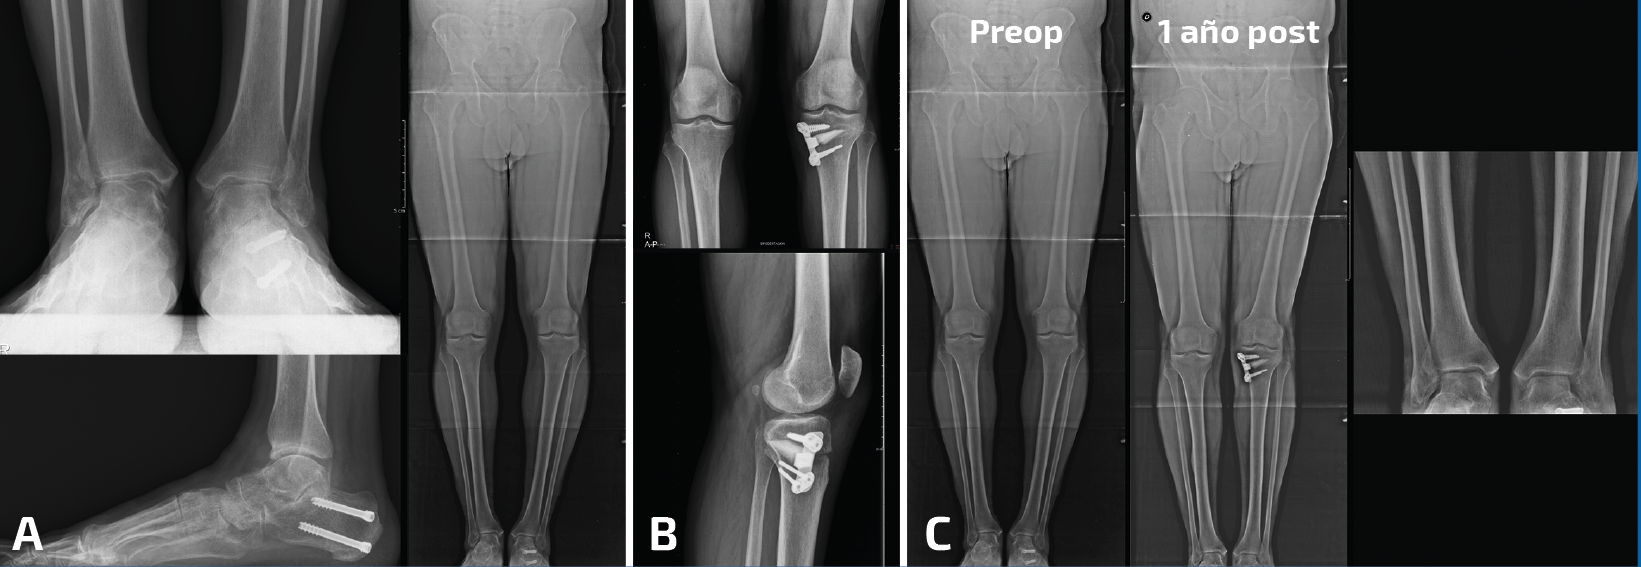

- El paciente tiene un genu varo con una rodilla asintomática y dolor en el tobillo/pie. Esta situación es más complicada porque, aunque creamos que la corrección proximal es la clave para la mejora del tobillo/pie, remitimos al paciente a nuestros colegas de rodilla y nos lo “devuelven” diciendo que si no hay dolor no hay indicación de cirugía en la rodilla. Y es, de alguna manera, comprensible. En estos contados casos, hemos realizado nosotros la osteotomía de tibia proximal para poder corregir el eje de carga de la extremidad con la esperanza de modificar el trabajo anómalo del tobillo. En algunos pacientes ya se había realizado una cirugía en el retropié. En la mayoría de nuestros pacientes hemos observado una mejoría muy notable (Figura 1).

Figura 1. Paciente con genu varo ya operado por pie plano valgo con coalición tarsal y tobillo doloroso. A: se realizó una osteotomía varizante de calcáneo; B: la mejoría después de la cirugía del retropié fue insuficiente y se realizó una osteotomía valguizante de tibia proximal; C: imágenes radiológicas al año de la cirugía. El paciente se encontraba asintomático de su tobillo, que había mejorado también en apariencia radiológica.